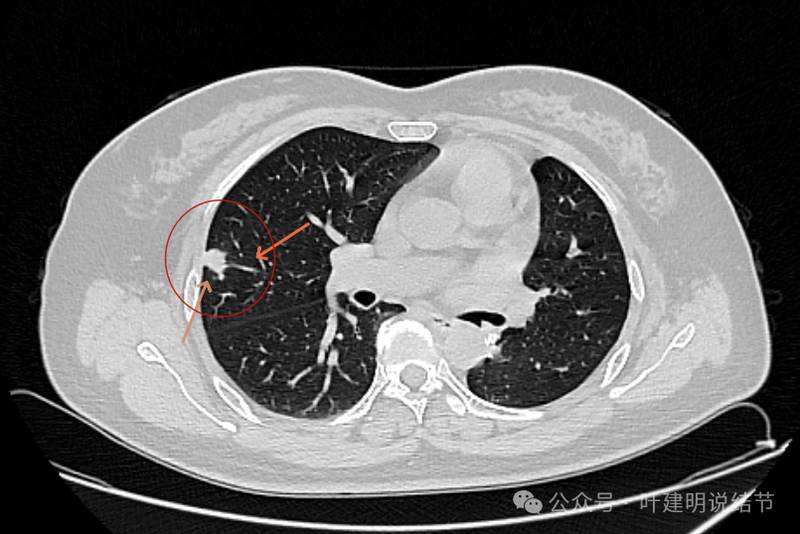

此层见病灶轮廓较清,有小血管进入,表面不平,有一定的膨胀感。部分边缘较为光滑。

胸膜间隙征存在,整体边缘显得较为光滑。

似乎两个中心点,密度均是实性的。

两个中心,病灶边缘光滑,轮廓清楚。